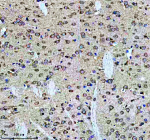

Immunohistochemical staining of Tuberin/TSC2 (Phospho-S939) using anti-Phospho-Tuberin (pSer939) antibody. Tuberin/TSC2 (Phospho-S939) was detected in a paraffin-embedded section of mouse brain tissue. Heat mediated antigen retrieval was performed in EDTA buffer (pH 8.0, epitope retrieval solution). The tissue section was blocked with 10% goat serum. The tissue section was then incubated with a dilution of 1:50 rabbit anti-Phospho-Tuberin (Ser939) antibody overnight at 4oC. Peroxidase Conjugated Goat Anti-rabbit IgG was used as secondary antibody and incubated for 30 minutes at 37oC. The tissue section was developed using an HRP secondary and DAB substrate.